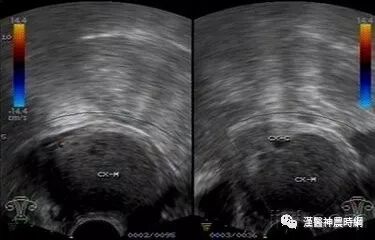

B超声象图:B超显象是目前辅助诊断子宫内膜异位症的有效方法,主要用以观察卵巢子宫内膜异位囊肿,其声象图的特征为:囊性肿块,边界清晰或不清。如囊肿周围粘连重,则边界不清;如囊肿与子宫或周围组织粘连少,则边界清晰。囊肿多为中等大小,囊肿内可见颗粒状细小回声,是囊液粘稠表现。有时因陈旧性血块浓缩机化而出现较密集的粗光点图象,呈混合性肿块状。

肿块常位于子宫后侧,可见囊肿子宫伴随症。囊肿自发破裂时,声象图示后凹陷,囊肿较前缩小。腹腔镜检查:腹腔镜检查是目前诊断子宫内膜异位症的新标准,通过腹腔镜可直接窥视盆腔,见到异位病灶即可明确诊断,且可进行临床分期,以决定治疗方案。